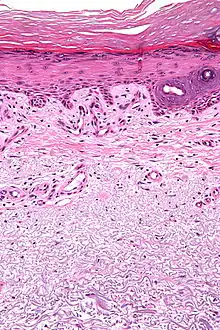

| Micrograph showing solar elastosis - grey, jumbled spaghetti-like material on bottom of image. H&E stain. | |

In the earlier stages of actinic elastosis, elastic fiber proliferation can be seen in the dermis. As the condition becomes more established, the collagen fibers of the papillary dermis and reticular dermis become increasingly replaced by thickened and curled fibers that form tangled masses and appear basophilic under routine haematoxylin and eosin staining. These fibers stain black with the Verhoeff stain.[2]